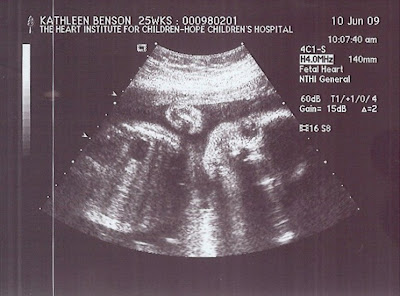

Good afternoon! I am checking in to let you know that we had our 25 week (gestation) echocardiogram (echo) this morning. Baby Benson’s heart looked great and normal according to the tech and our perinatal cardiologist! They both seemed glad to see us and to be able to deliver such wonderful news! Bob and I felt blessed and lucky to receive the news about our baby girl. It was bittersweet to be back in that examining room for what will likely be the last time with this pregnancy (if everything continues to proceed normally, as it has so far). Being on that table while the tech did the echo today brought back so many memories of the times we spent there during our pregnancy with Molly last year. It was surreal to be there and to get such awesome news about our new baby, which she confirmed is “definitely a girl.”

Baby Benson (pictured here in her latest ultrasound photo) moved around a lot during the echo and much of the time I could feel her doing so. It made it more difficult for the tech to get some of the pictures and measurements that she needed to initially, but it was a good and “normal” problem for her to have. This was unlike with many of our our echos with Molly, when because of our daughter’s heart being so weak, she often wasn’t moving very much, especially towards the end. By the time our perinatal cardiologist came in to see how everything looked and how we were doing I was in tears (both those of joy and those of missing Molly). She understood and was very supportive — telling us how happy she was for us and reiterating how she believes that our first daughter has had a hand in helping to bring our second daughter to our family.